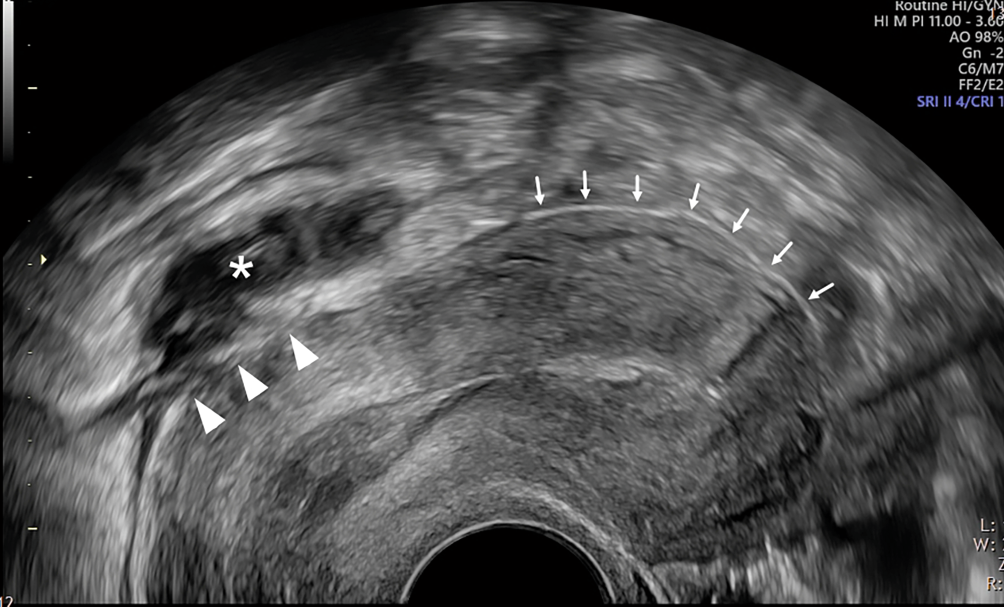

Abb. 3

„Tail“, „tent“ und „omega sign“. Im Querschnitt beschreibt die WSL an der Uterusoberfläche eine Art Igluzelt („tent sign“, b). Die seitlichen Ausläufer schlagen lateral schwänzchenartig nach kranial um (rechts und links „tail sign“, ac). Insgesamt ergibt sich daraus das „omega sign“ (ac), welches eine grossflächige Beurteilung des Peritoneums im kleinen Becken mit einer klaren Darstellung der Beckenwand erlaubt. abd. abdominal, rp. retroperitoneal, Ut. Uterus

Bild vergrößern

Wird der Griff der Vaginalsonde nun etwas angehoben oder abgesenkt, kann die gesamte posteriore Uterusserosa von der Zervix bis zum Fundus auf Endometrioseläsionen abgesucht werden, welche sich meist als unregelmässig geformte, hypoechogene Bereiche oder Unterbrechungen der WSL präsentieren; Endometrioseläsionen können sich jedoch sehr heterogen als glatt oder unscharf begrenzt darstellen und entweder eine homogene oder heterogene Textur aufweisen [12]. Entlang der gesamten Serosa muss, wie beschrieben, ein positives „sliding“ zu den umliegenden Organen darstellbar sein.

Nun kann der Griff der (immer noch um 90 Grad gedrehten) Vaginalsonde etwas nach rechts (respektive links) bewegt werden, um den Bereich links (respektive rechts) der WSL zu beurteilen (laterales Kompartiment). Das „tent sign“ der WSL geht dabei nach lateral nahtlos auf das Peritoneum der Beckenwand über und beschreibt dabei eine schwänzchenartige Kurve nach oben („tail sign“, Abb. 3a, c). Über die gesamte Breite des kleinen Beckens ergibt sich somit die Abfolge „tail-tent-tail“, was aneinandergereiht etwa der Form eines Omegas entspricht („omega sign“, Abb. 3a–c).